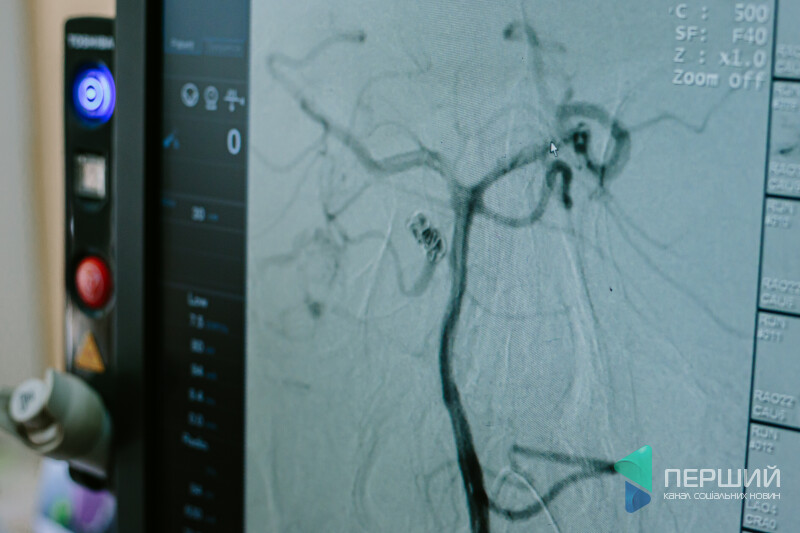

До того ж, за словами Юрія Легкодуха, цей ангіоаграф відкрив нові горизонти. Він дозволяє проводити складні операції на судинах головного мозку, сонних артеріях. Під час оперативного втручання демонструє карту судин, вказуючи на уражене місце:

«Уявіть собі величезне дерево з безліччю гілок, яке нагадує мережу судин людини. Щоб потрапити катетером до потрібної судини, треба спочатку її знайти. Нова ангіографічна установка дозволяє це робити максимально ефективно».

«Філіпс» показує лікарям у рази якіснішу «картинку», дозволяє оцінити вогнище ураження, розпізнати атеросклеротичну бляшку, побачити проблеми судин.

«Наприклад, є аневризма у головному мозку. Щоб у неї зайти і закрити спіраллю чи запломбувати, треба доволі багато морочитися, бо вона тоненька. Новий ангіограф дав можливість якісніше робити такі оперативні втручання. Вражає 3D-зображення. Ми можемо у тривимірному форматі дивитися усі судини та проблеми у них, збільшувати та досліджувати з різних боків. А наскільки легше, коли зроблену і записану на диск комп’ютерну томографію головного мозку можна закласти в сам ангіограф і з цим працювати!» – ділиться враженнями від роботи Юрій Легкодух.